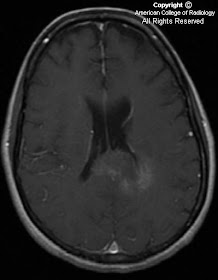

Figure 1, Figure 2, Figure 3, and Figure 4 demonstrate a hypointense T1, hyperintense T2 weighted expansile mass involving the splenium of the corpus callosum. The mass has well defined borders and partially effaces the atrium (trigone) of the left lateral ventricle. There is mild patchy enhancement (Figure 4). DWI images demonstrate increased signal throughout, but only the even more hyperintense rim (Figure 5) demonstrates true restricted diffusion on ADC images (Figure 6). The remainder of the mass is increased signal on ADC images, indicating increased diffusivitiy.

The abnormality in our case does illustrate a few of these characteristics, such as a circumscribed border and lack of surrounding edema. The lesion did demonstrate increased diffusivity on DWI/ADC maps, which would argue against a highly cellular tumor like lymphoma and a high grade glioma. Active foci of demyelination may demonstrate restricted diffusion. In our case, the thin peripheral rim of restricted diffusion may represent an active edge of demyelination. The mass effect on the atrium of the left lateral ventricle is a confounding factor that can be associated with tumefactive demyelination or neoplasms. Metastases usually elicit a large amount of edema which was noticeably absent in this case. Infarction is also unlikely given the patient’s age and based on the imaging characteristics of the abnormality. Infarctions involving the corpus callosum are uncommon because of the ample blood supply from the anterior and posterior circulation. Unfortunately, none of these features is specific enough to warrant watchful waiting, and therefore a biopsy was performed.